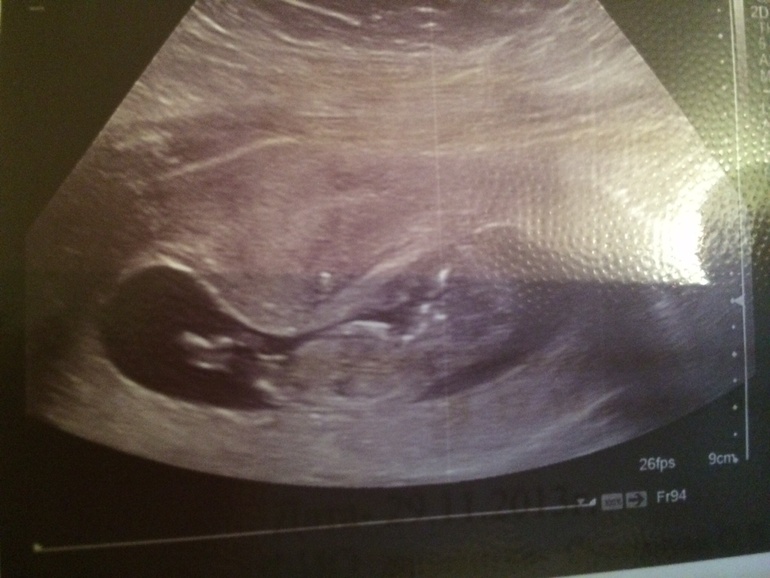

Вопросы про УЗИ, обследования и анализы: что, где, как, когда?Сегодня сделала узи 11.3 все в норме только очень переживаю за серцебиение 185!!!!!

А у меня М были 12.09 и сегодня 11.1 а по узи ктр 47,6мм поэтому 11,3-11,4